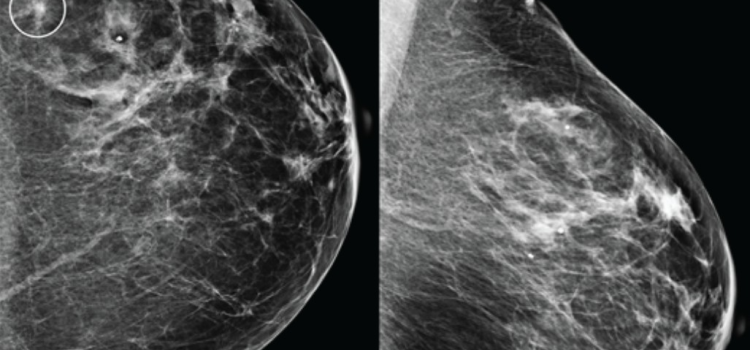

Mammography

Mammography is a breast imaging technique that uses X-rays to diagnose and locate tumors of the breasts.

Early detection is key to breast cancer survival. But nearly half of all women in the U.S. have dense breast tissue ...